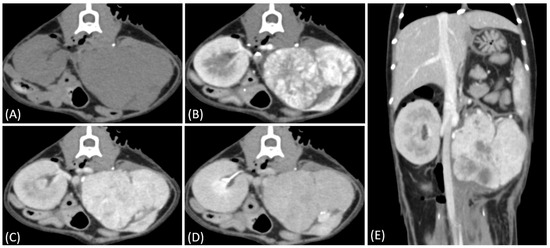

Figure 2.

(A) Pre-contrast, (B) corticomedullary phase, (C) nephrographic phase, and (D,E) late nephrographic/early excretory phase contrast-enhanced computed tomography (CT) images of a cat with a unilateral left renal cell carcinoma. The tumor demonstrates predominantly heterogeneous and plateau enhancement patterns throughout the phases, with focal areas of intense enhancement visible during the corticomedullary phase.